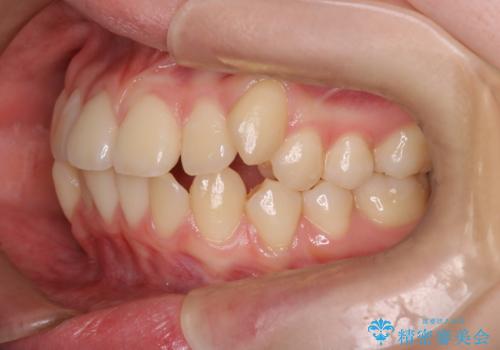

- 八重歯が気になるとのことでご相談いただきました。診察すると、歯列のスペース不足により犬歯が外側に飛び出している状態でした。このままでは歯を並べるスペースが足りないため、抜歯矯正が必要と判断。治療は目立ちにくいインビザラインで行い、歯の移動をサポートするためにゴムかけ(顎間ゴム)を併用する計画を立てました。

抜歯後、インビザラインを用いて少しずつ歯を移動させ、空いたスペースに八重歯を整列させました。さらに、ゴムかけを行うことで上下の噛み合わせを適切に調整。治療後は、八重歯が綺麗に並び、バランスの取れた歯並びと自然な噛み合わせを実現できました。患者様にも「仕上がりがとても綺麗で、口元の印象が変わった」とご満足いただきました。